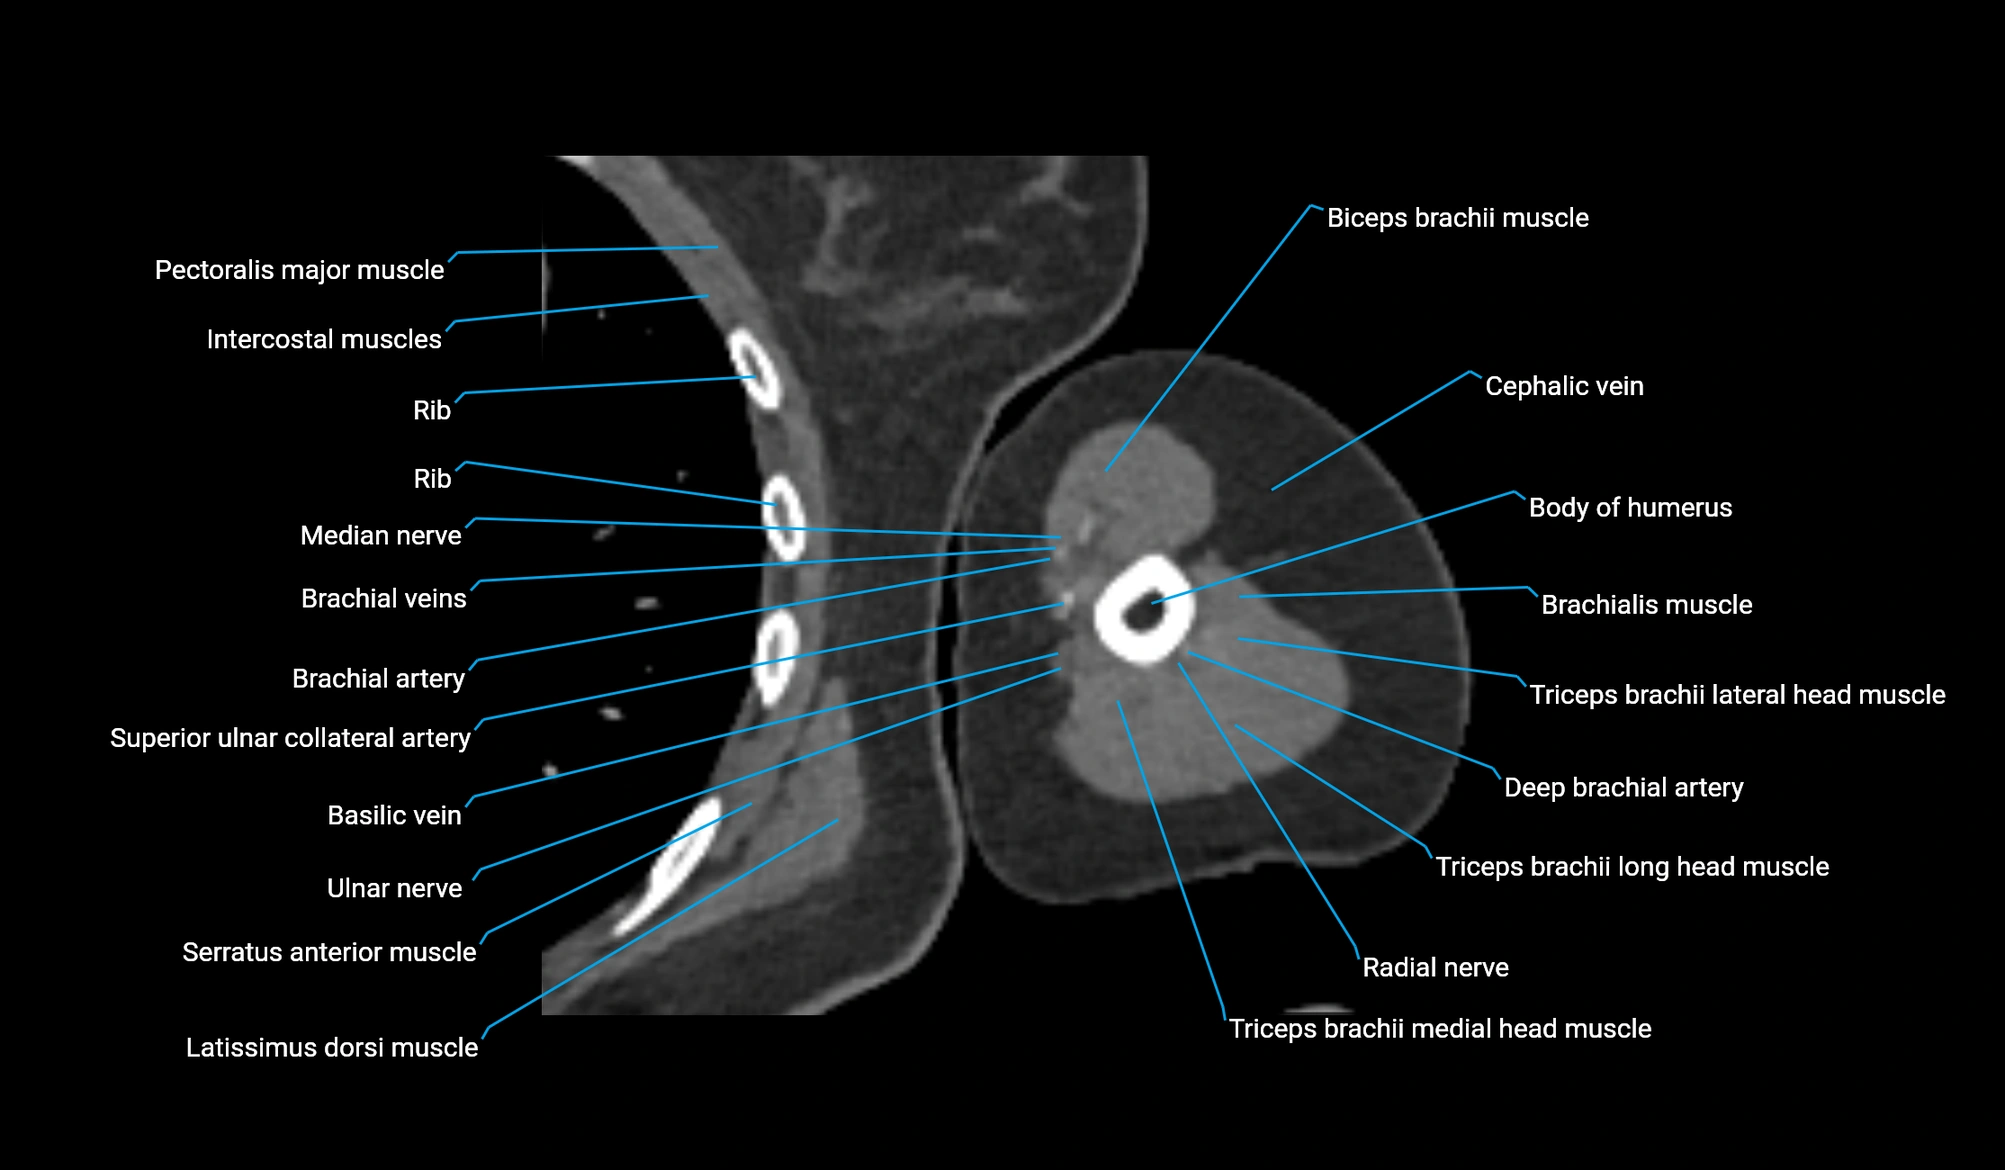

- Body of humerus

- Brachial artery

- Brachialis muscle

- Cephalic vein

- Deep brachial artery

- Median nerve

- Radial nerve

- Superior ulnar collateral artery

- Ulnar nerve